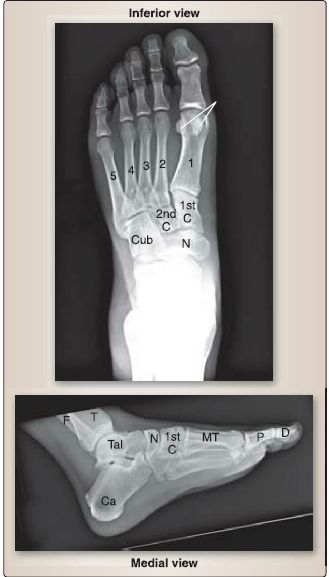

Joints of the foot are numerous and include the subtalar, talocalcaneonavicular, calcaneocuboid, cuneonavicular, tarsometatarsal, intermetatarsal, metatarsophalangeal, and interphalangeal joints (Fig. 9). Figure 10 shows plain film of the foot and bones.

Figure 9: Foot joints. Supporting ligamentous structures. IP = interphalangeal joints,

MTP = metatarsophalangeal joints, TMT = tarsometatarsal joint.

Figure 10 : Plain film radiographs of normal foot. C = cuneiform, Ca = calcaneus, Cub = cuboid, D = distal phalange, F = fibula, MT= metatarsals (1-5), N = navicula,P = proximal phalange, T = tibia, Tai = talus.